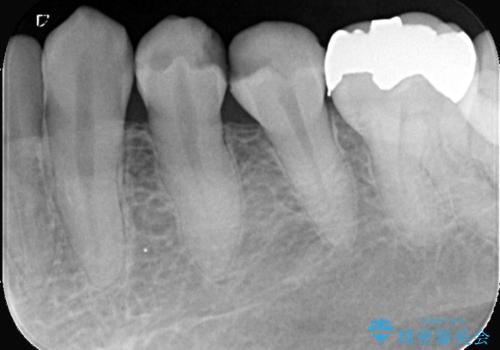

- CRが劣化し欠けてしまっている状態でした。 虫歯を除去後、歯を破折から守るためオールセラミッククラウンで治療を行いました。

- 税込264,000円(オールセラミッククラウン121,000円×2本+仮歯11,000円×2本)費用は治療当時の料金となります